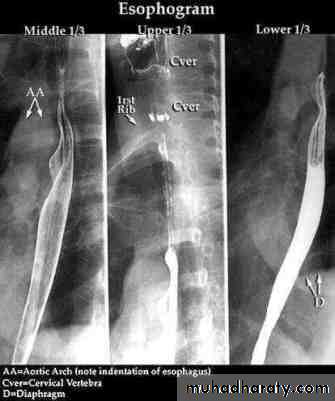

Esophagus: This muscular tube extends 25 cm from the cricoid cartilage to the cardiac orifice of the stomach. It has an upper and a lower sphincter. it is lined by stratified squamous epithelium. The muscle layers of the upper esophagus are striated skeletal muscle, while the muscles of lower part are smooth. A peristaltic swallowing wave propels the food bolus into the stomach. DISEASES OF THE ESOPHAGUS

Investigations Chest X-ray; widening of the mediastinum, aspiration pneumonia.A barium swallow; tapered narrowing of the lower esophagus, esophageal body is dilated, aperistaltic and food-filled.Endoscopy; must always be carried out, carcinoma of the cardia can mimic the presentation and radiological and manometric features of achalasia ('pseudo-achalasia').Manometry; confirms the high-pressure, non-relaxing lower esophageal sphincter with poor contractility of the esophageal body.

Investigations Endoscopy; The investigation of choice, with cytology and biopsy.Barium swallow ; site and length of the stricture .Thoracic and abdominal CT Endoscopic ultrasound (EUS)